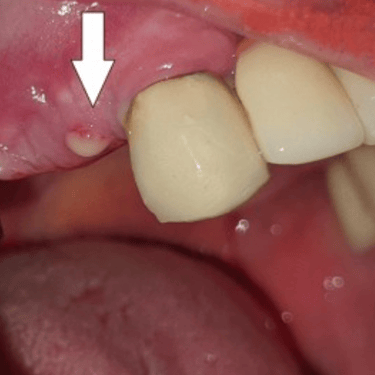

Implantes dentales fracasados

Los implantes dentales fracasados son aquellos que no se han integrado correctamente con el hueso o han desarrollado complicaciones postoperatorias.

Los pacientes pueden notar movilidad en el implante, dolor o inflamación.

El tratamiento puede incluir la extracción del implante fallido y la preparación para un nuevo implante.